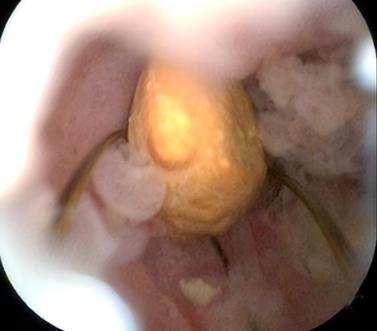

摘要:目的 探讨一次性子母胆道镜辅助内镜逆行阑尾炎治疗术在急性非复杂性阑尾炎治疗中的诊断和治疗价值。方法 回顾性分析2022年9月-2024年9月该院内镜中心通过一次性子母胆道镜辅助内镜逆行阑尾炎治疗术治疗的39例急性非复杂性阑尾炎患者的临床资料,观察内镜下表现、子母网篮取石率、阑尾支架置入率、技术成功率、临床成功率、手术时间、住院时间、并发症发生率和术后6 h视觉模拟评分法(VAS)评分,以及术后24 h炎症指标。结果 28例(71.8%)患者结肠镜下阑尾开口可见充血和水肿,10例(25.6%)患者结肠镜下阑尾开口可见脓液流出,32例(82.1%)患者子镜下阑尾腔内可见大量脓液,20例(51.3%)患者子镜下阑尾腔内可见粪石;一次性子母胆道镜辅助内镜逆行阑尾炎治疗术的技术成功率为100.0%(39/39);手术时间(21.08±7.49)min;住院时间(3.97±2.08)d;8例(20.5%)患者行内镜下子母网篮取石术;14例(35.9%)患者行阑尾支架置入术。临床成功率为97.4%(38/39),1例患者术后临床症状和炎症指标未缓解,转外科行阑尾切除术。38例患者术后6 h的VAS评分 < 3分,腹痛症状明显缓解;术后24 h白细胞计数和中性粒细胞百分比较术前明显下降,差异均有统计学意义(P < 0.05);39例患者均未发生并发症;术后随访(5.94±4.03)个月,3例(7.7%)出现复发。结论 一次性子母胆道镜辅助内镜逆行阑尾炎治疗术诊断和治疗急性非复杂性阑尾炎,安全且有效,值得临床推广应用。